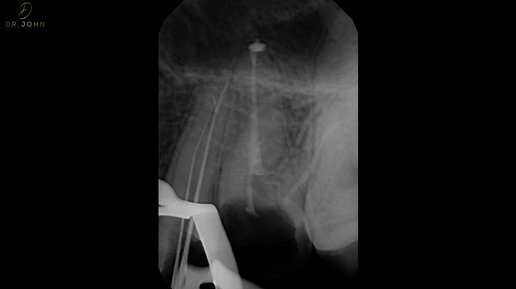

Острый пульпит верхнего премоляра